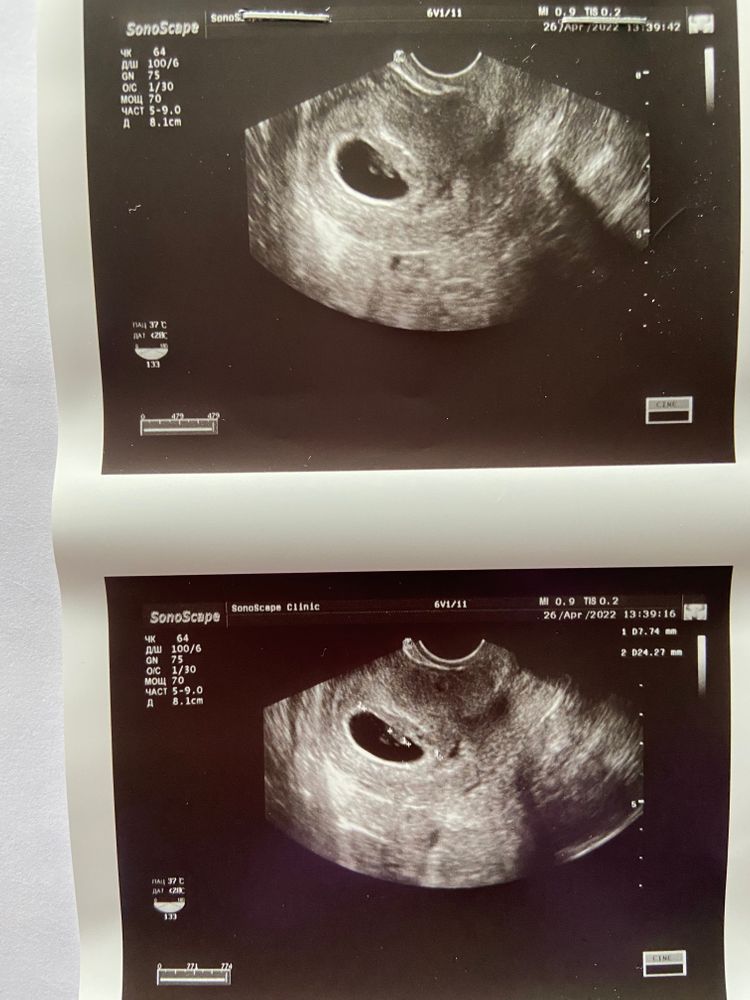

Прошла неделя, пошла на узи, все хорошо, нашли малыша❤️ Изображение

26.04.2022

Меня только смущает что жм не указано,но по фото,вроде как есть